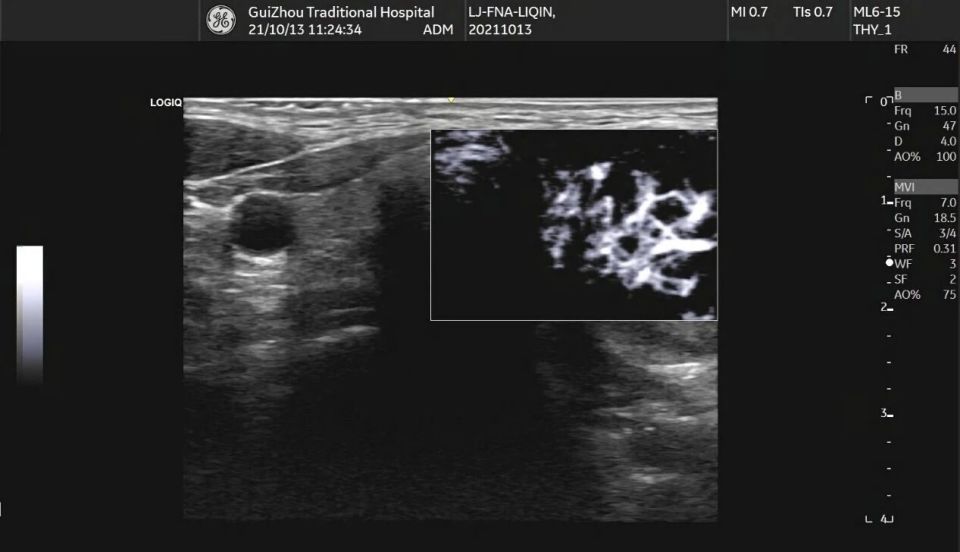

在甲状腺超声里,有好些小于1毫米的亮点,这些亮点有隐藏重要信息的可能,这些叫做点状强回声,有时这些点状强回声后方带着呈逐渐减弱态势的平行线条,样子类似彗星尾巴,这种情况通常是浓缩胶质形成的混响伪像,然而实际诊断时,医生常碰到既无声影又无可观察彗尾征的强回声点,这时判断其性质就特别困难了。

点状强回声出现,其后方伴有声影,这属于典型的微钙化表现,多条平行强回声存在,向深部延伸,这是由浓缩胶质形成的彗星尾伪像,然而在临床实践当中,这两种特征并非总是如此典型,小于1毫米的微钙化,可能不会产生明显声影,给准确判断造成了难度 。

点状强回声的位置意义

结节在不同部位,那里出现了然点状强回声,而其临床意义有着截然不同的情况, 在位于囊性部分的体现为短线状强回声,尤其是伴有典型彗尾征的那种,大多是由浓缩胶质形成的,这属于良性表现,这些胶质实际上是甲状腺滤泡内浓缩的胶状性质物 。

点状强回声出现在实性部分时,此显示情况下其后方没有清楚明显的彗尾征,这时需十分密切高度警惕微钙化存在的可能性,在这样的状况下,即便结节其他特征表现展示良好,也应按可疑特征样式处理应对,还建议更进一步深入检查明确定性质,。